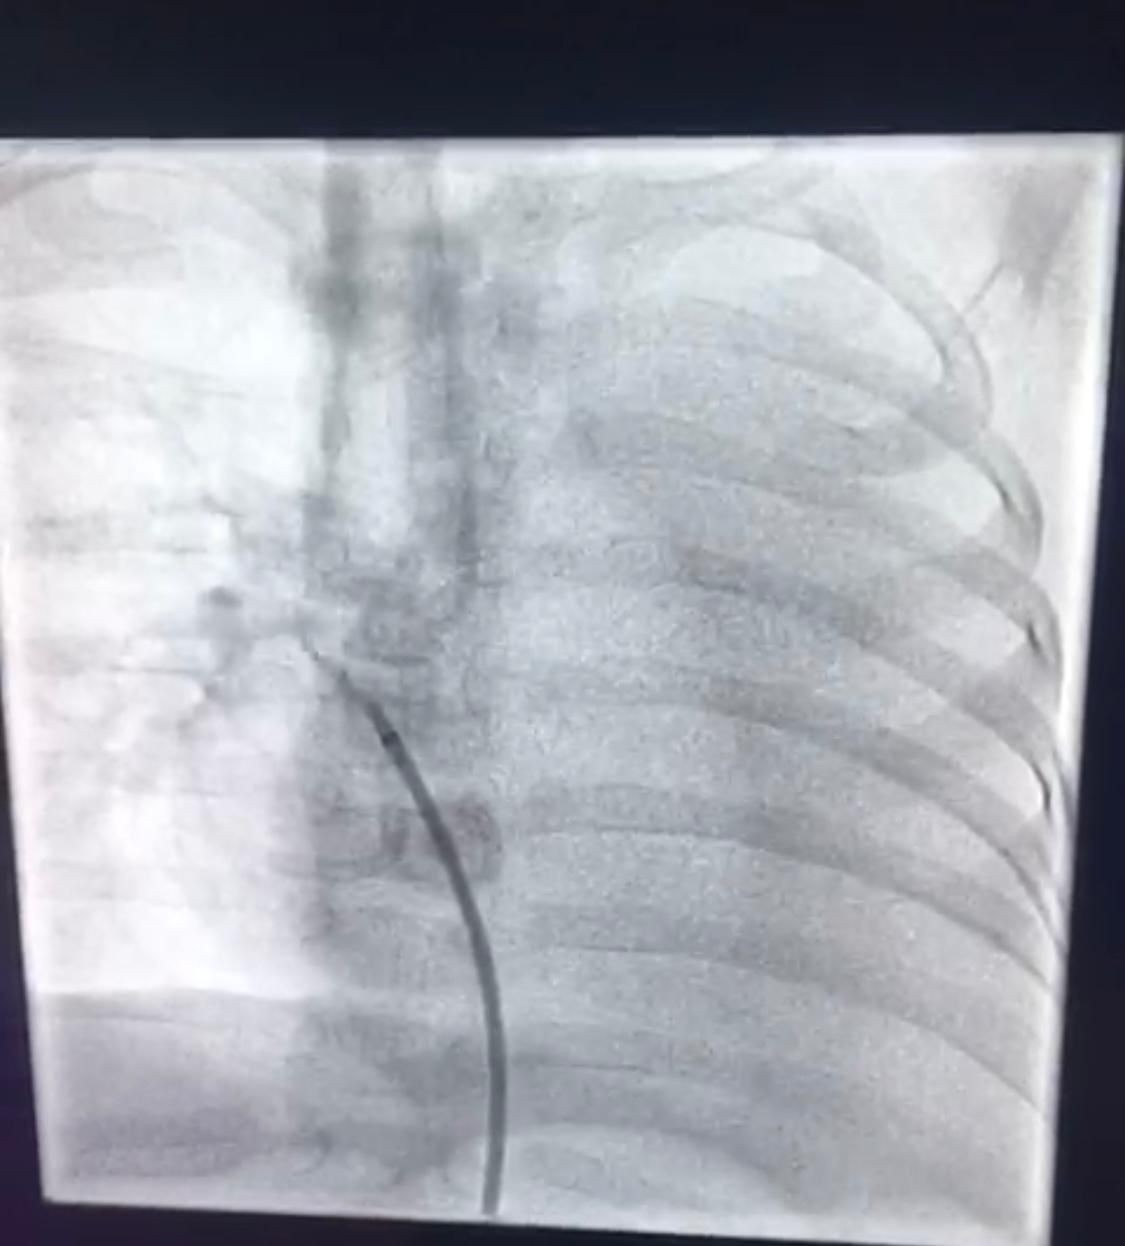

وأوضح مدير مركز أم القرى للقلب بمستشفى الولادة والأطفال بمكة الدكتور خالد أمين العطاس: من بداية الخطة العلاجية تم إعطاء الطفل أدوية لعلاج السوائل ثم تم فحصه بجهاز أشعة القلب "إيكو"تم إكتشاف وجود شريان زايد يأتي من الشريان الأورطي النازك إلى الأُذين الأيسر في القلب وهذه "القناة تعتبر من القنوات النادرة جداً" أن يكون مصب الدم من الأورطه مباشرة إلى الجهه اليسرى من القلب مباشرة وعليه تم عمل قسطرة تشخيصية لمحاولة إقفال القناة بجهاز خاص وتكللت العملية بنجاح ولله الحمد بفضل من الله حيث مكث الطفل مدة يومان للتأكد من سلامة القدم .وأستمرت متابعة الطفل حتى بعد خروجه من المستشفى للأطمئنان على صحته.